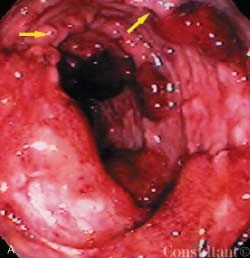

For 6 weeks, a 29-year-old previously healthy man had between 10 and 15 episodes daily of small-volume bloody diarrhea with intermittent paraumbilical pain. Colonoscopy revealed diffuse ulceration with loss of vascularity and mucosal surfaces that extended from the rectum to the cecum. Pseudopolyps-distinct, irregular, raised areas of normal-appearing mucosa-were noted among the areas of friability, fibrous stranding, and ulceration. Pseudopolyps, which represent a combination of reactive hyperplasia and mucosal ulceration, are not uncommon in severe or chronic ulcerative colitis.